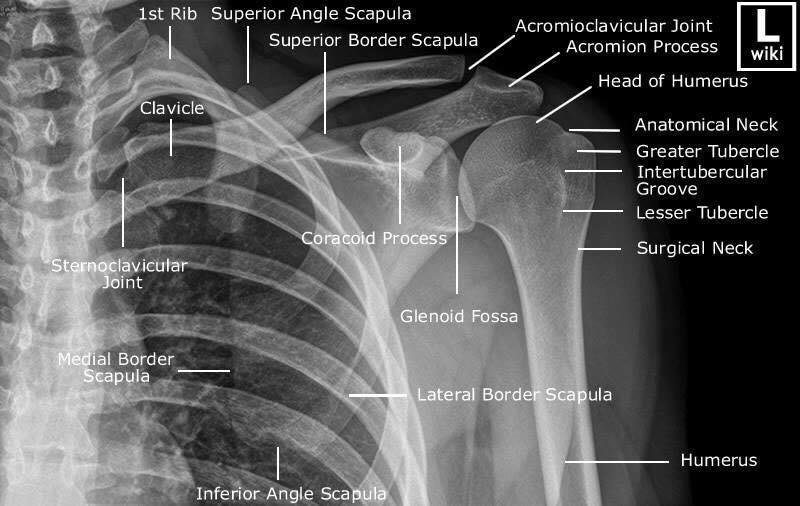

Las radiografías, generalmente llamadas rayos X, producen imágenes como sombras de huesos y ciertos órganos y tejidos. Las radiografías son muy buenas para detectar problemas óseos. Pueden mostrar algunos órganos y tejidos blandos; sin embargo, la MRI y la CT suelen crear mejores imágenes de los mismos. Aun así, las radiografías son rápidas, fáciles de obtener y menos costosas que los otros estudios, por lo que se pueden usar para obtener información rápidamente.

Un tubo especial dentro de la máquina de rayos X emite un haz de radiación controlada. Los tejidos del cuerpo absorben o bloquean la radiación en diferentes grados. Los tejidos densos como los huesos bloquean la mayor parte de la radiación, pero los tejidos blandos, como la grasa o los músculos, bloquean menos radiación. Después de pasar por el cuerpo, el haz alcanza una pieza de un fragmento de película o un detector especial. Los tejidos que bloquean altas cantidades de radiación, como los huesos, aparecen como áreas blancas en un fondo negro. Los tejidos blandos bloquean menos radiación y aparecen en tonos de gris. Los órganos que contienen principalmente aire (como los pulmones) aparecen en negro. Los tumores son por lo general más densos que el tejido que los rodea, por lo que suelen verse en tonos grises más claros.